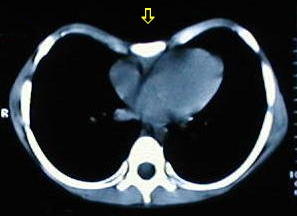

Tomografía de tórax

• Corte tomografico a nivel del tercio superior del torax, supracarinal.

• Corte tomografico a nivel carinal, comienza a insinuarse la depresión esternal.

• A medida que descienden los cortes, se observa la mayor depresión esternal.